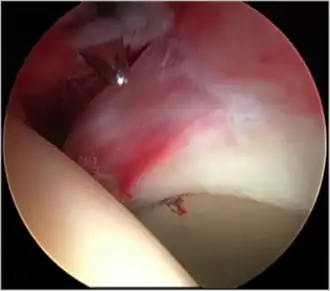

Labral tears

The acetabular labrum is a fibrous structure, which surrounds the femoral head. It forms a seal to the hip joint,[15] although its true function is poorly understood. Recent evidence has demonstrated that this hydraulic seal is vital for maintaining stability of the ball and socket joint [16] and reducing contact pressures of the femur to the acetabulum.[17] The labrum has also been shown to have a nerve supply and as such may cause pain if damaged.[18] The underside of the labrum is continuous with the acetabular articular cartilage so any compressive forces that affect the labrum may also cause articular cartilage damage, particularly at the junction between the two, the chondrolabral junction. The labrum may be damaged or torn as part of an underlying process, such as FAI or dysplasia (shallow hip socket), or may be injured directly by a traumatic event. Depending on the type of tear, the labrum may be either trimmed (debrided) or repaired. Removing or debriding the labrum is becoming less popular as the latest research shows that results are more predictable in the long term if the labrum can be repaired. Various techniques are available for labral repair, mainly using anchors, which may be used to re-stabilise the labrum against the underlying bone, allowing it to heal in position.

New techniques are prevalent in hip arthroscopy. There is good evidence to support the creation of a new labrum by performing a labral reconstruction if the patient has previously had a labral debridement, has an ossified labrum, or the current labrum is too small or injured for a repair.[16] Labral reconstruction involves creating a new labrum either from the patients own tissue (autograft) or from cadaver tissue (allograft). The new labrum is then anchored into position with bone anchors and the hip then goes through extensive rehab.